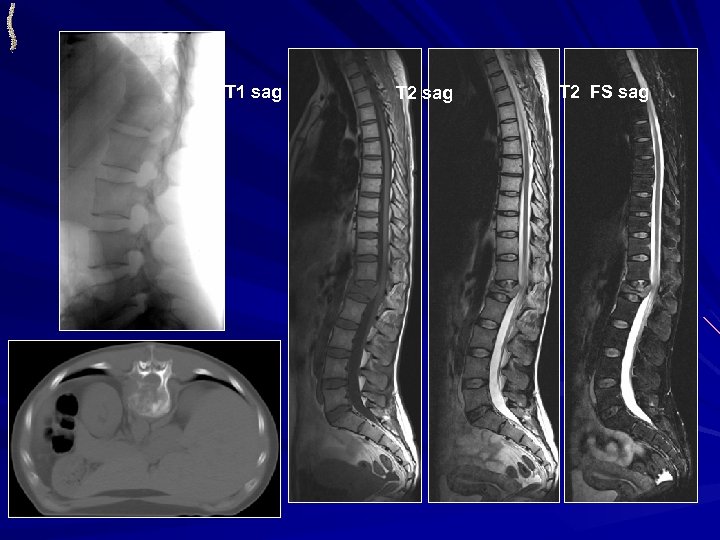

МЕТАСТАЗЫ РАКА ПОЧКИ • МОГУТ ПРОЯВЛЯТЬСЯ ЧЕРЕЗ МНОГО ЛЕТ ОТ ПЕРВИЧНОЙ ОПУХОЛИ • ЧАСТО ПОРАЖАЮТСЯ ДЛИННЫЕ ТРУБЧАТЫЕ КОСТИ КТ: Костная деструкция преимущественно литического или ячеистого типа Вздутие коркового слоя Солитарность поражения МРТ: Солитарность поражения Неоднородная солидная структура очагов Наличие в структуре патологических сосудов Чаще всего массивный внекостный компонент

МЕТАСТАЗЫ РАКА ПОЧКИ T 2 sag MPR cor T 1 sag T 2 FS sag MPR sag L 1 Патологические сосуды в структуре метастаза